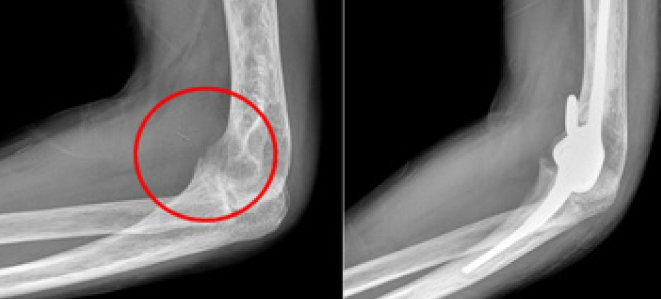

팔꿈치 치환술 (Total Elbow Arthroplasty)

적응증: 팔꿈치 관절 전치환술은 심한 팔꿈치 관절염, 외상성 부상 또는 팔꿈치 관절에 영향을 미치는 특정 골절과 같은 상태에 대해 시행됩니다.

절차: 이 수술에서는 팔꿈치 관절의 손상된 부분을 금속 경첩을 포함한 인공 부품으로 교체합니다. 이를 통해 팔꿈치 움직임이 향상됩니다.

혜택: 팔꿈치 교체는 통증을 완화하고, 관절 안정성을 향상시키며, 팔꿈치 기능을 회복시켜 환자가 일상 작업을 더 쉽게 수행할 수 있게 해 줍니다.